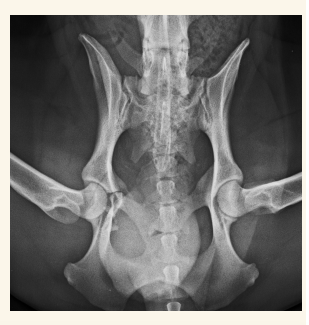

Pelvis

Fracturas y neoplasias lo mas comun. Hacer proyecciones LL, VD y Obliqua

Cadera

En general se hacen proyecciones:

- Ventro-dorsal: Extender extermidades y traccionar, sin rotación axial, paralelas a la mesa, buscamos que la rotula se superponga con el surco troclear. Posicion de rana si es una fractura pelvica

- Latero-Lateral: Esponja de gomaespuma entre rodillas, estirar extermidades posteriores a caudal